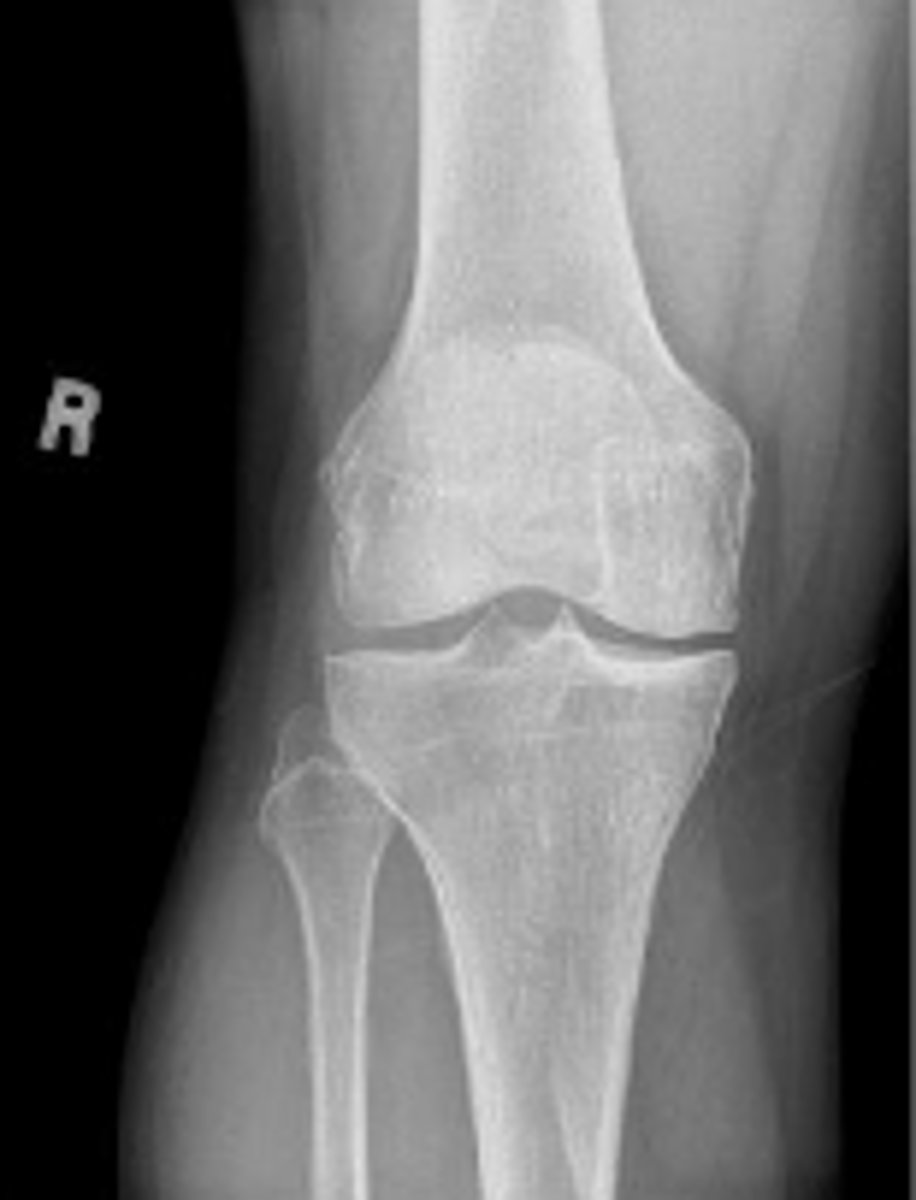

Right AP knee

What is the name of the radiographic view?